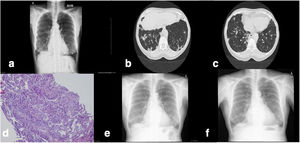

(a) The first chest X-ray upon admission of the patient. (b and c) An image of the lower lobes on CT during admission. (d) Transbronchial biopsy showing interstitial lymphocytic inflammatory infiltrate with eosinophils and pneumocyte hyperplasia. (e) Chest X-ray 4 weeks after treatment withdrawal with minimal infiltrates in the right lower lobe. (f) Chest X-ray 3 months after withdrawal of flecainide and corticosteroid treatment. It does not present infiltrates.

A 74-year-old woman was admitted due to one month of irritative cough and dyspnea on exertion (mMRC 1 point). She denied fever or contact with SARS-CoV-2-positive individuals. She suffered from chronic atrial fibrillation, due to poor rhythm control and the presence of palpitations, she was treated with flecainide 100mg every 24h for 2 months. An elevation of the glomerular sedimentation rate of 95mm/h was found on the blood tests. On the chest X-ray patchy opacities in both lung bases were observed. The pandemic context made it necessary to rule out COVID-19 infection (Fig. 1a). In the initial study, two nasopharyngeal swabs with polymerase chain reaction (PCR) were performed for SARS-CoV-2 as well as for other respiratory viruses such as Influenza A, B, and respiratory syncytial virus (RSV). The result was negative. SARS-CoV-2 serologies were also performed and were both IgM and IgG negative. The microbiological study was completed with atypical pneumonia serologies (IgM and IgG from Coxiella burnetii and Mycoplasma pneumoniae) that were negative. Chest computed tomography (CT) was requested for a more thorough evaluation of the infiltrates, observing multiple pseudonodular ground glass areas with an apic-basal gradient. Multiple condensations of spiculated morphology with associated small traction bronchiectasis, predominantly on the right lung, were observed in both lower lobes (Fig. 1b).

Finally, a bronchofibroscopy was performed in order to expand the microbiological assessment with the culture of the bronchoalveolar lavage (BAL), considering less frequent microorganisms in immunocompetent patients such as Pneumocystis carinii, fungi, Mycobacterium tuberculosis, etc. Moreover, a transbronchial biopsy (BTB) for histopathological evaluation of the lesions was performed. Bronchofibroscopy did not show any alteration in the airway mucosa or mucopurulent secretions. In the LBA microbiological study, all cultures were negative, including a new PCR for SARS-CoV-2. The pathological anatomy of the BTB included four fragments of evaluable lung parenchyma. It presented a temporally homogeneous pattern of interstitial thickening with mature-appearing edema and lymphocytic inflammatory infiltrate that was accentuated around vascular structures. No significant fibrosis was found, but type 2 pneumocyte hyperplasia with prominent microvacuolization of cytoplasm was evident. In addition, a single intra-alveolar fibroblast nest with the absence of exudative or inflammatory components was seen. No granulomas were observed. GMS (silver) staining showed no fungal structures or Pneumocystis. A mixed pattern of organized pneumonia (NO) and non-specific interstitial pneumonia (NSIP) was described (Fig. 1c). The characteristics of the lesions pointed to a possible toxic-drug cause.

After completing the study and with the diagnosis of flecainide pneumonitis, the withdrawal of the drug was decided, changing to diltiazem to control his baseline tachyarrhythmia. Corticosteroid treatment was started with 30mg of oral prednisone every 24h, tapering the dose in the following weeks. A week later, the patient's condition improved substantially, her cough and dyspnea disappeared, she had mild side effects of the corticosteroid treatment such as insomnia and anxiety that gradually disappeared with the progressive decrease in the dose. After 4 weeks, she was reevaluated in the outpatient clinic. The X-ray showed a decrease in the infiltrates, and some scar images on the right base (Fig. 1d). Respiratory function tests were also performed in which she had a normal CO diffusion of 104%. In the subsequent follow-up, the patient remained asymptomatic. She was able to withdraw the prednisone treatment and after 3 months she showed a complete resolution of the radiologic infiltrates (Fig. 1e).